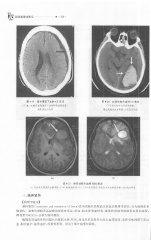

Page 314 - 医学影像诊断学